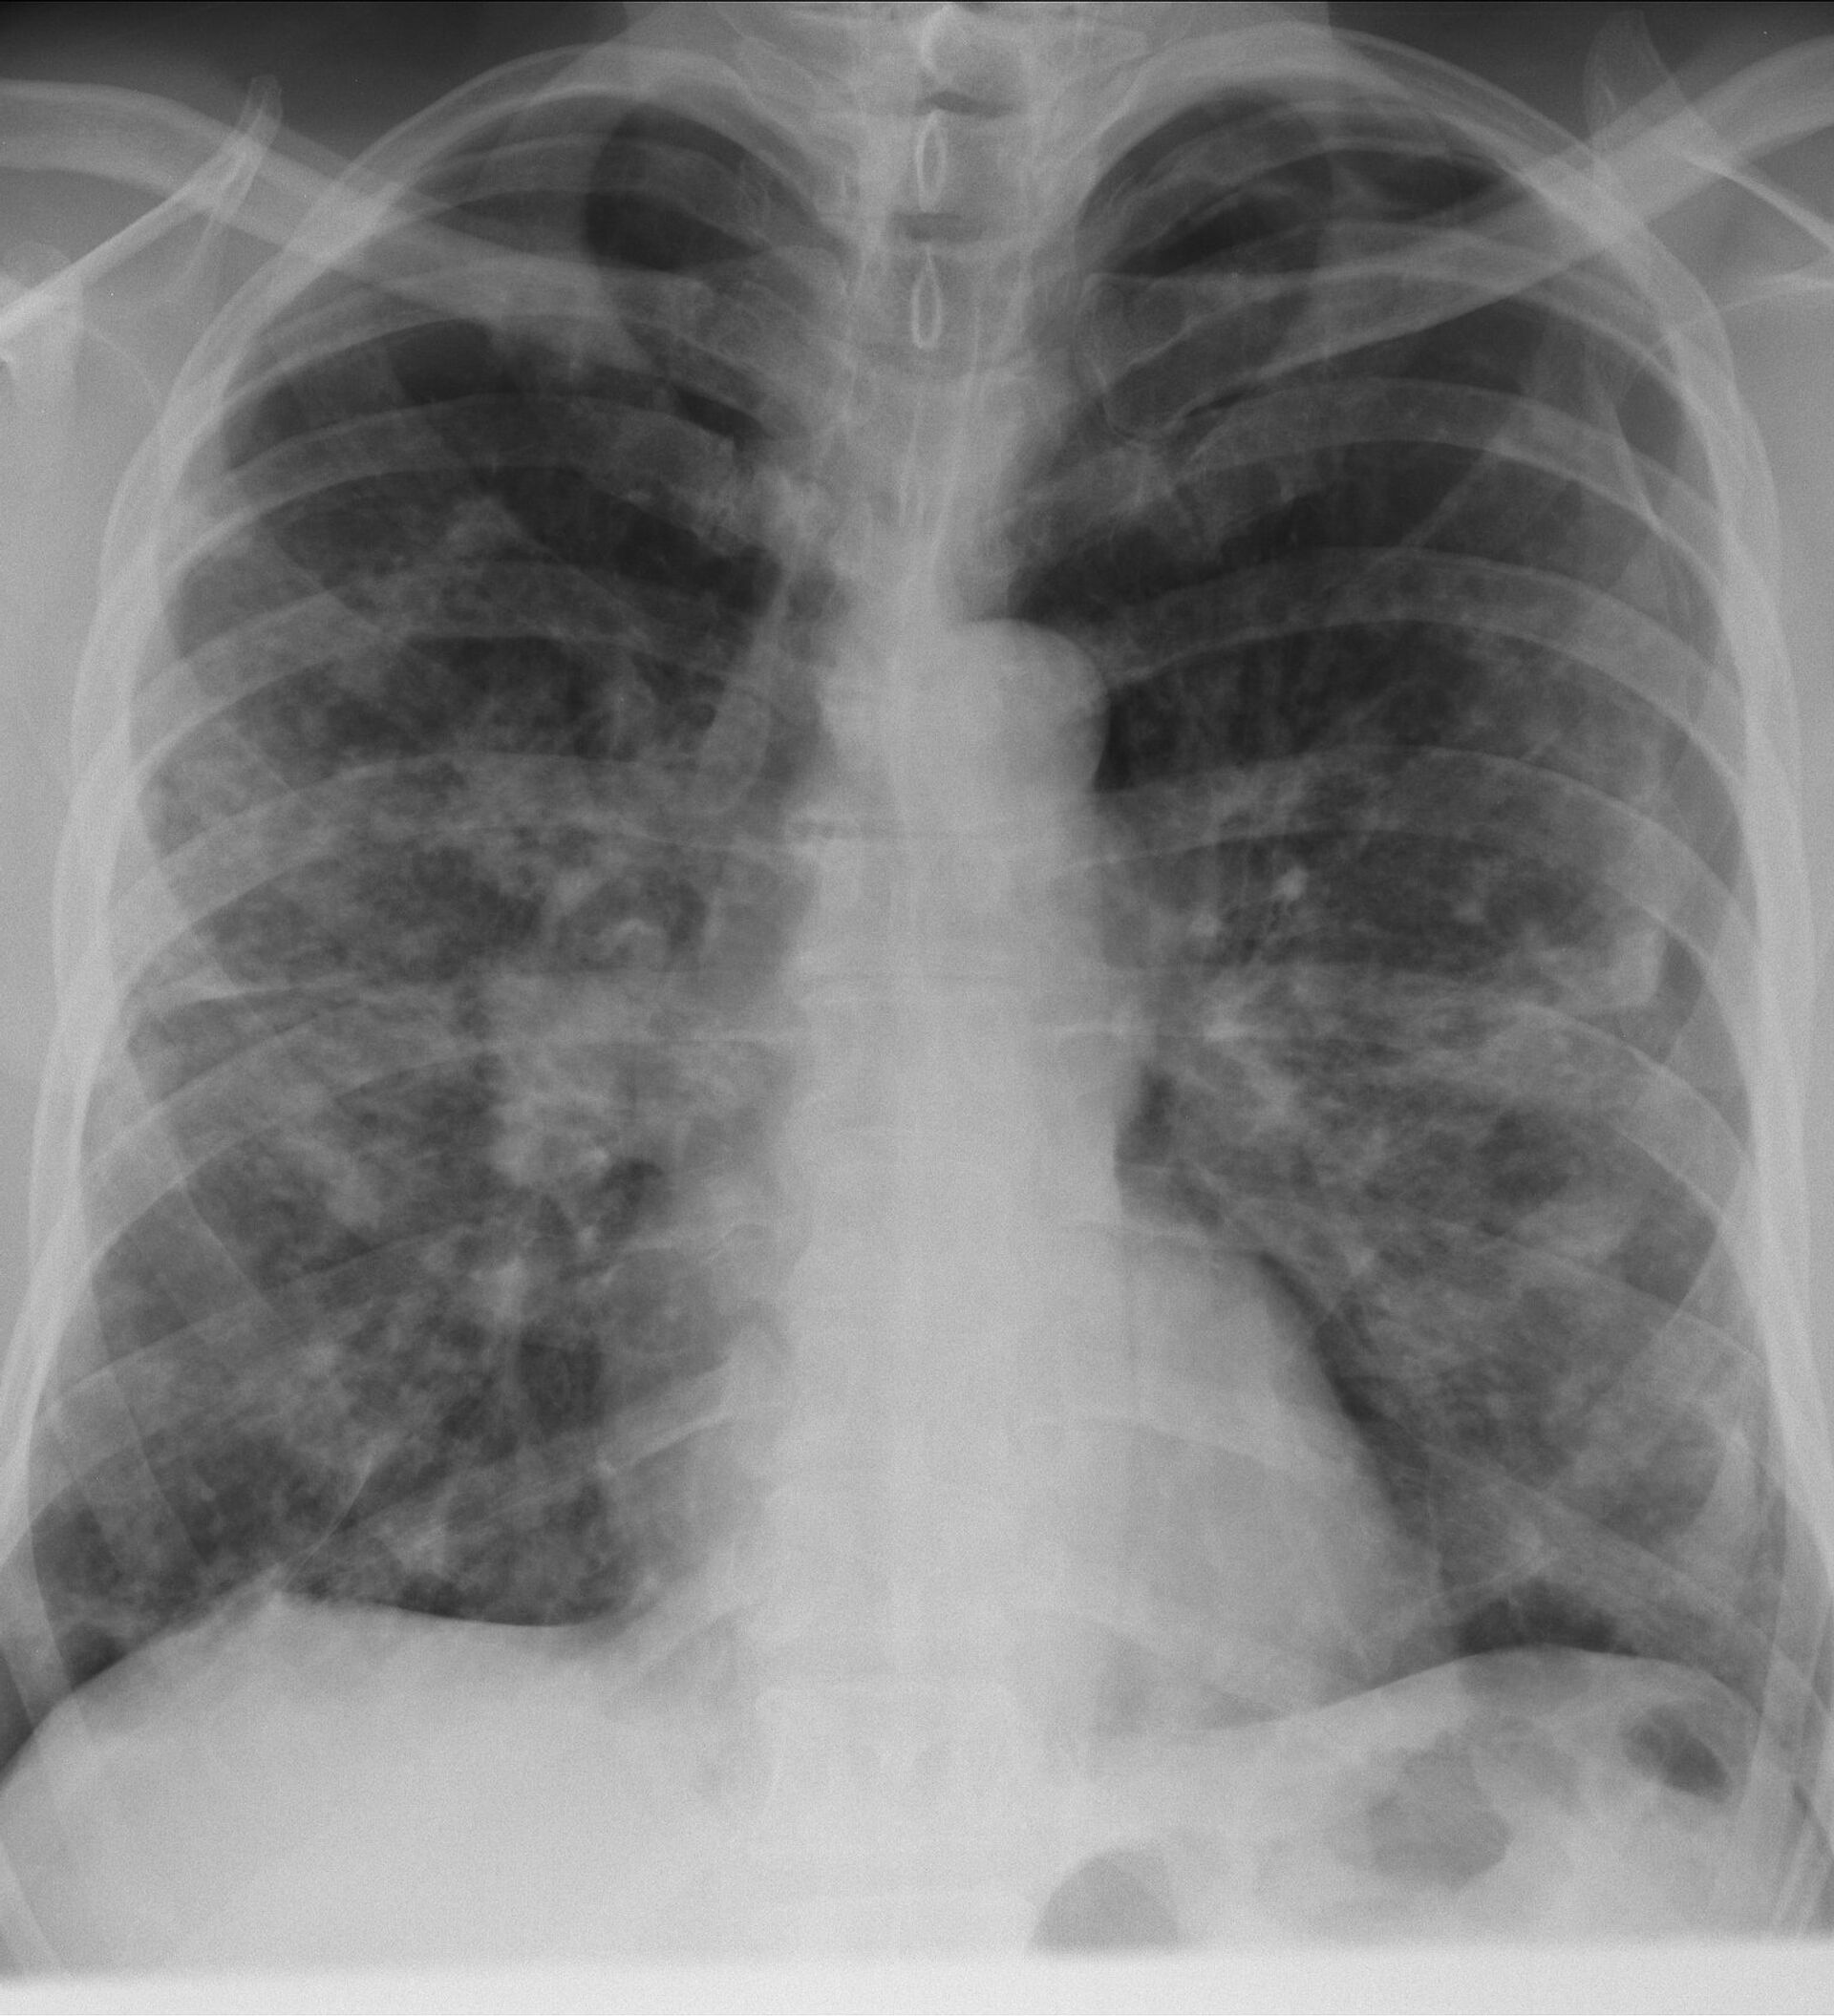

Este nuevo sistema puede ayudar a detectar el cáncer de pulmón de una manera rápida, eficiente y no invasiva, algo que hasta ahora era imposible.

El cáncer de pulmón es uno de los más mortíferos entre las enfermedades cancerosas. En Rusia se registran unos 60.000 casos de cáncer de pulmón al año. Y la posibilidad de detectarlo a tiempo podría ser la diferencia entre la vida y la muerte.